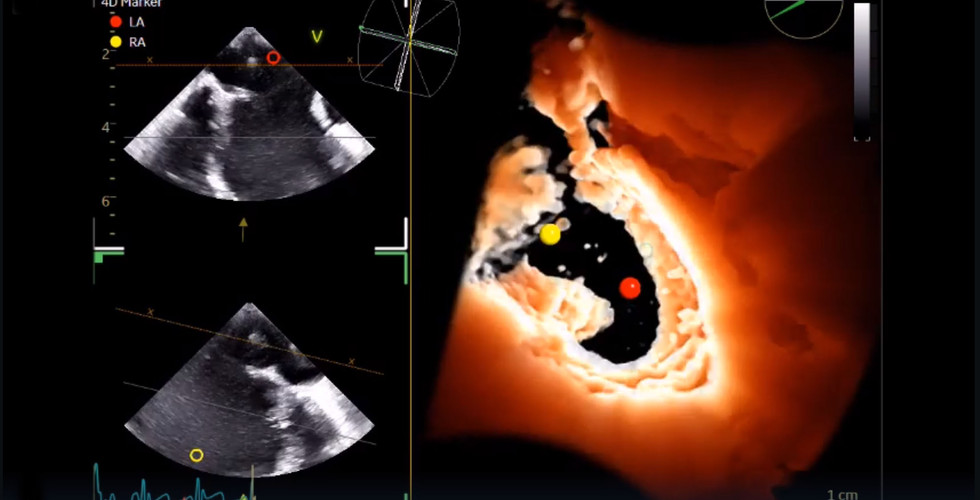

3D TEE je sonda určená pro širokou škálu pediatrických a intervenčních zákroků a pro pacienty o hmotnosti již od 5 kg, která současně nabízí všechny režimy 2D, 4D, barevný a dopplerovský; kardiologické, pediatrické a koronární aplikace a to s hloubka snímání až 18 cm.

3D ultrazvuková vizualizace má zásadní význam pro zlepšení diagnostické jistoty, pochopení morfologie srdce pacientů a vedení zákroků. Nejkompaktnější 3D mini TEE sonda na světě je vhodná pro širokou škálu intervenčních kardiologických zákroků a potenciálně eliminuje potřebu celkové anestezie u dospělých pacientu.

Hodnocení dětských pacientů s vrozenými srdečními vadami vyžaduje hluboké znalosti srdečních struktur. 3D TEE může poskytnout realističtější vizualizaci ve srovnání s 2D TEE. Použití 3D TEE může zlepšit předoperační plánování, nabídnout vodítko a pomoci při funkčním hodnocení srdce. Miniaturizace 3D TEE umožňuje její použití u pacientů o hmotnosti pouhých 5 kg.